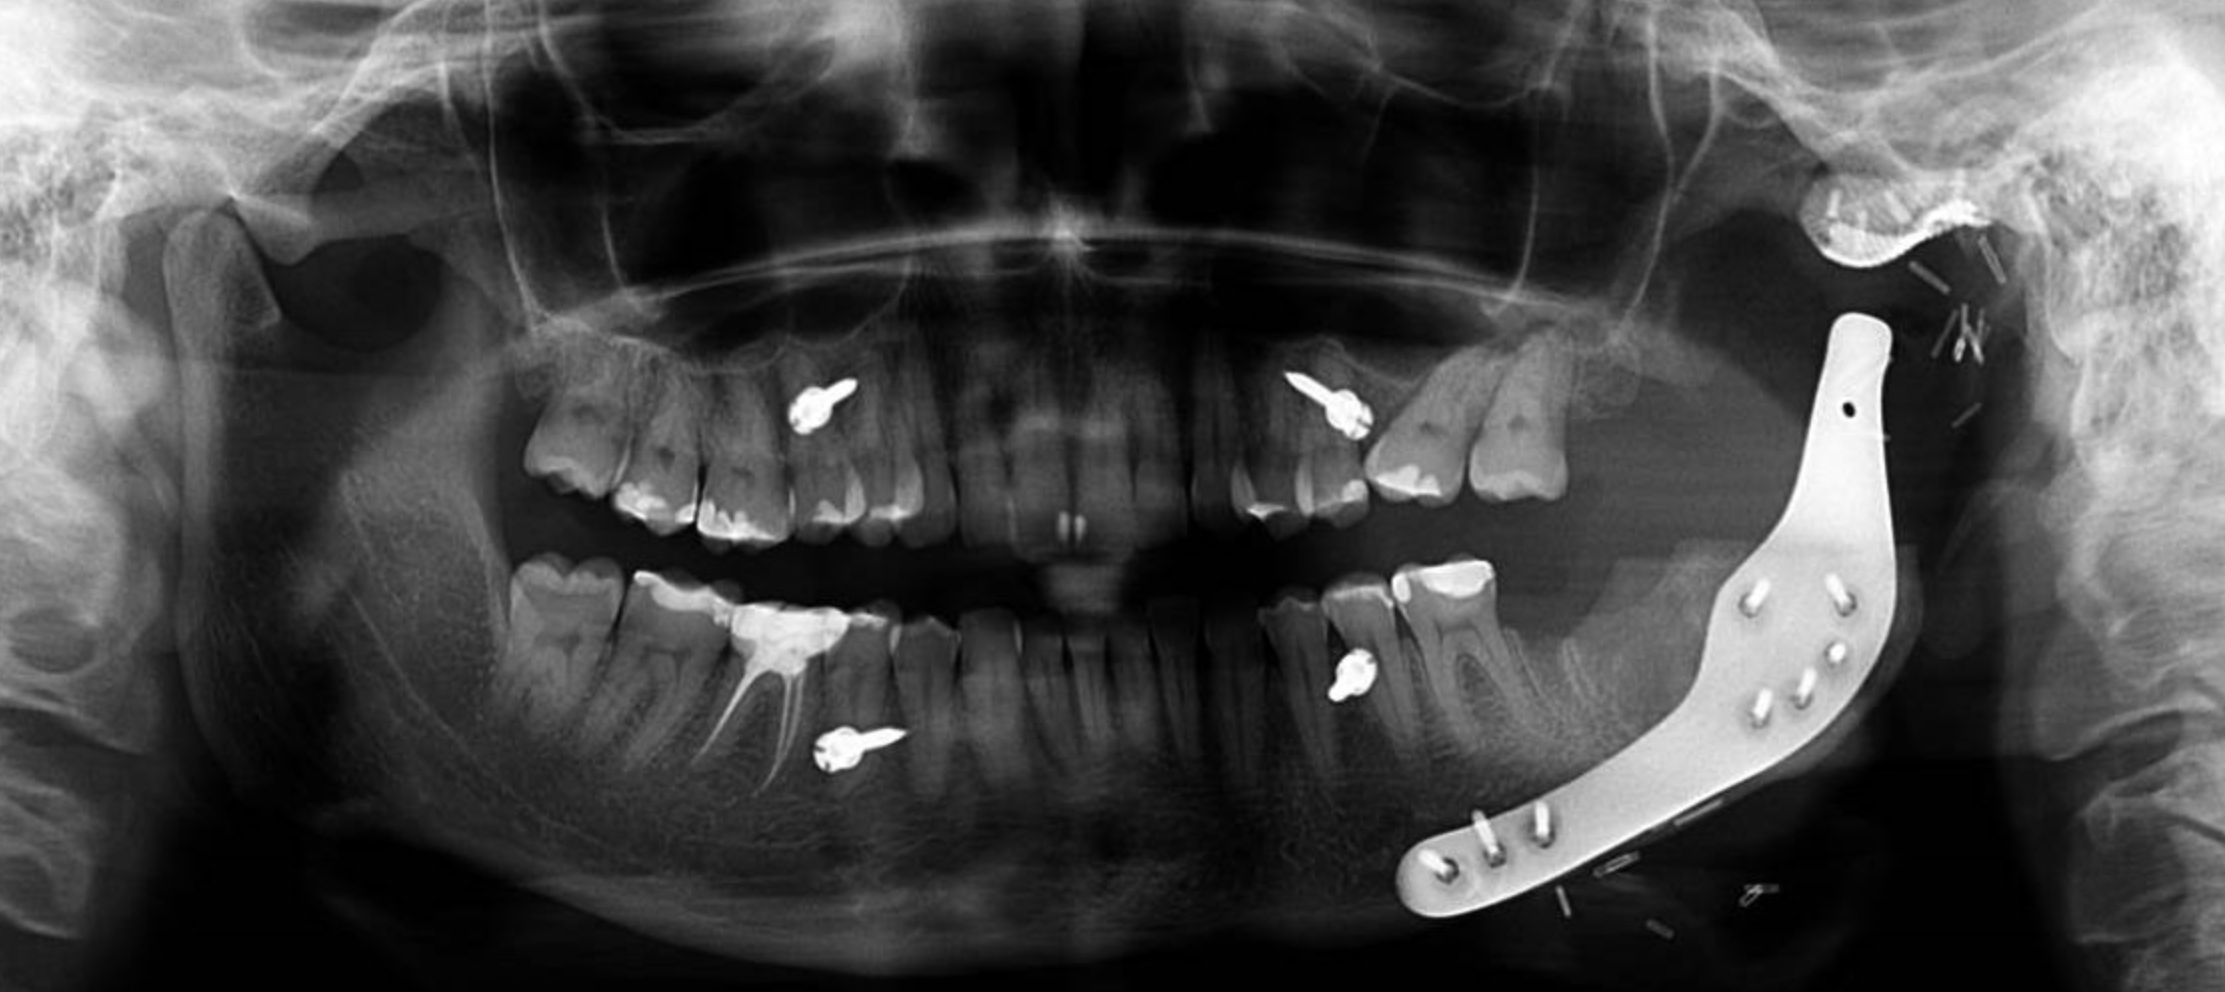

Keratocysts can show much higher recurrence rates than other cyst types. Simple enucleation can lead to a higher propensity for recurrence. Add to this the fact that keratocysts can escape to involve adjacent soft tissues, and more definitive treatment is often warranted to minimise the chance of things coming back. Adjuncts that have traditionally been used include peripheral ostectomy (removal of the surrounding bone) and/or chemical agents such as Carnoy’s solution. In particularly aggressive lesions, segmental resection may be required. The case shown required a custom alloplastic extended temporomandibular joint replacement (eTMJR) from Stryker Ventura TMJ Concepts for a multiply recurrent odontogenic keratocyst with associated pathological fracture on the condyle. As a comprehensively trained specialist in Oral and Maxillofacial Surgery with a subspecialty interest in TMJ surgery, all the options are available to make sure there is the best chance of success in even the most challenging cases.